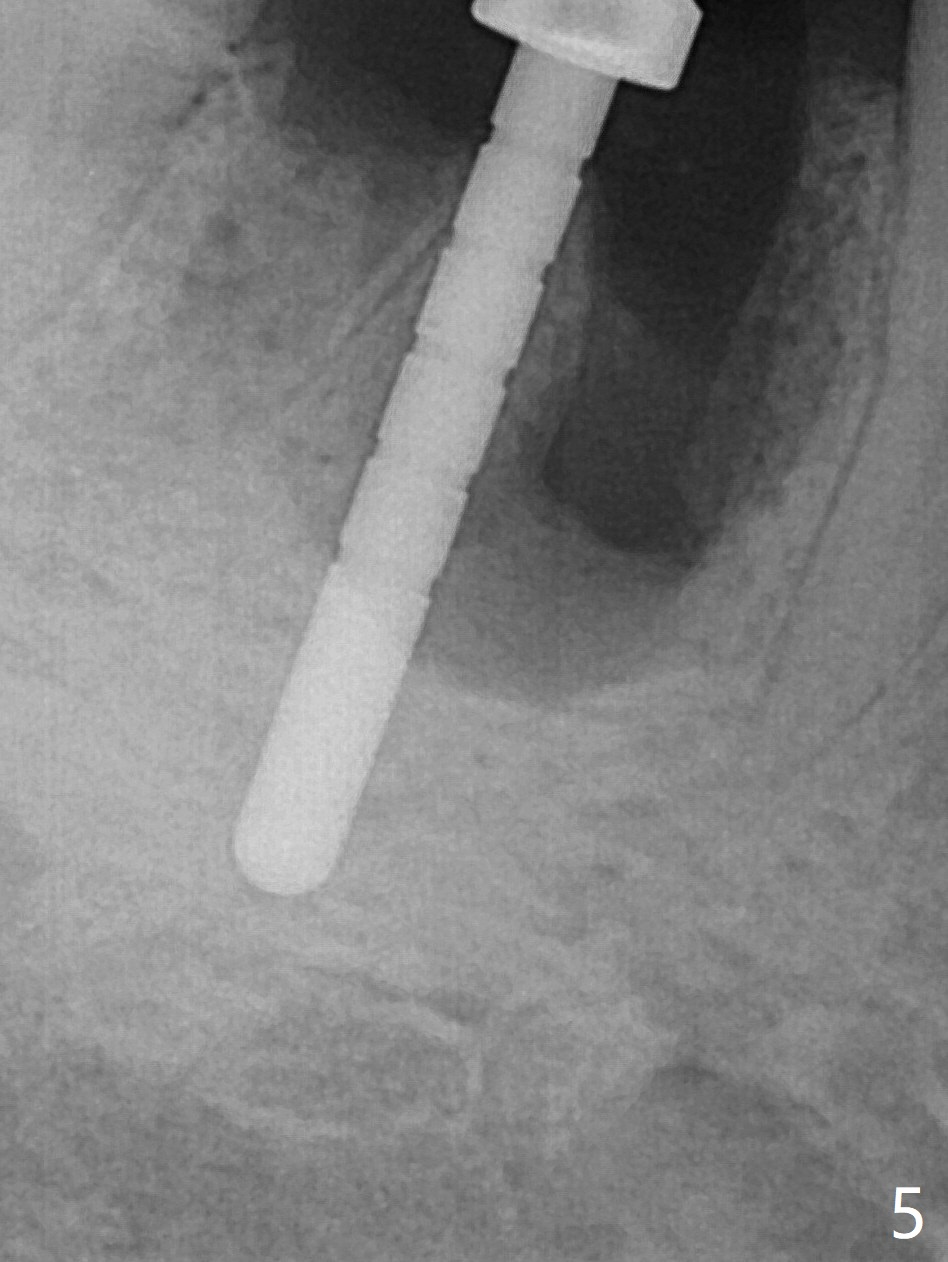

Preop oral Amoxicillin seems to be associated with reduction in the buccal and lingual (Fig.3 arrow) fistulae at #30, but there is mesiobuccal swelling (Fig.1 *) with 7 mm pocket (Fig.2). Osteotomy is initiated in the middle of the septum (Fig.3-5 S). As the osteotomy increases, it shifts mesially (Fig.6 arrow). Guided surgery is able to reduce shifting. A 5x13 mm implant is not seated completely (Fig.7) apparently due to osteotomy shifting. After removal of the bone from the osteotomy distally, the implant remains unseated with lower torque value (Fig.8). Following reuse of the 4.3 mm drill deeper by 1-2 mm, the implant is seated to a satisfactory depth (Fig.9 with increase in torque to 50 Ncm) with placement of Vera Graft (*) and a 7.5x4(3) mm abutment. After a second round of allograft placement (Fig.10 *), the implant is found to be 4 mm from the IAC. At the later stage of osteotomy, the coronal end of the septum is destroyed with loss of osteotomy depth landmark. It is apparent that the soft tissue landmark may be more reliable. The implant threads appear to be covered by the bone graft 3.5 months postop (Fig.11). The abutment is changed to 6.5x5(3) mm one before impression with minor margin prep. The bone density seems to increase 5 months postop, i.e., immediately post cementation (Fig.12) and 10 months postop (5 months post cementation (after retightening abutment), Fig.13 (*)). Periimplantitis develops mesiobuccally, consistent with bone loss 1 year 7 months post cementation (Fig.14 *); the implant seems to have been buccally placed. Bone graft is necessary with PRF or GEM21S if the vein is small and 6-month membrane with a hole around a 7.5x4(4) cemented abutment for easy wound closure. Take 5x5 CM CBCT to determine which wall has defect, buccal or lingual. Check mesial contact. If so, remove the crown, reseat the abutment (possible incomplete seating) and re-impress after bone graft.